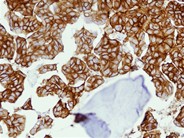

A 36-year old man presented with abdominal tenderness and pain in both legs. He had no significant medical history and was using acetaminophen and opioids for his pain. A CT-scan showed no abnormalities except for diffuse sclerosis of the lumbar spine and pelvic bones,  which could fit the diagnosis of myelofibrosis, metabolic disorder or malignancy (A). A bone marrow biopsy showed 100% cellularity (B). Using the Gomori trichrome staining, grade 2 fibrosis was demonstrated. However, there was no splenomegaly and the abdominal pain was not understood. A PET-CT scan showed metabolically active mediastinal and hilar lymph nodes. A histological biopsy showed CK7-positive epithelial cells with the typical morphology of signet ring cells (C). Subsequently a gastroscopy confirmed the diagnosis of gastric cancer. With this finding, an additional staining on the bone marrow biopsy also showed solitary signet ring cells (D). He was thus diagnosed with gastric cancer with lymph node and bone marrow metastases. Previously, secondary myelofibrosis had been described as a rare paraneoplastic syndrome. The clinical course was complicated by cerebral, kidney and spleen infarctions. His (neurological) condition deteriorated, possible due to new cerebrovascular events which occurred despite anticoagulant therapy, and unfortunately he passed away one month after presentation.